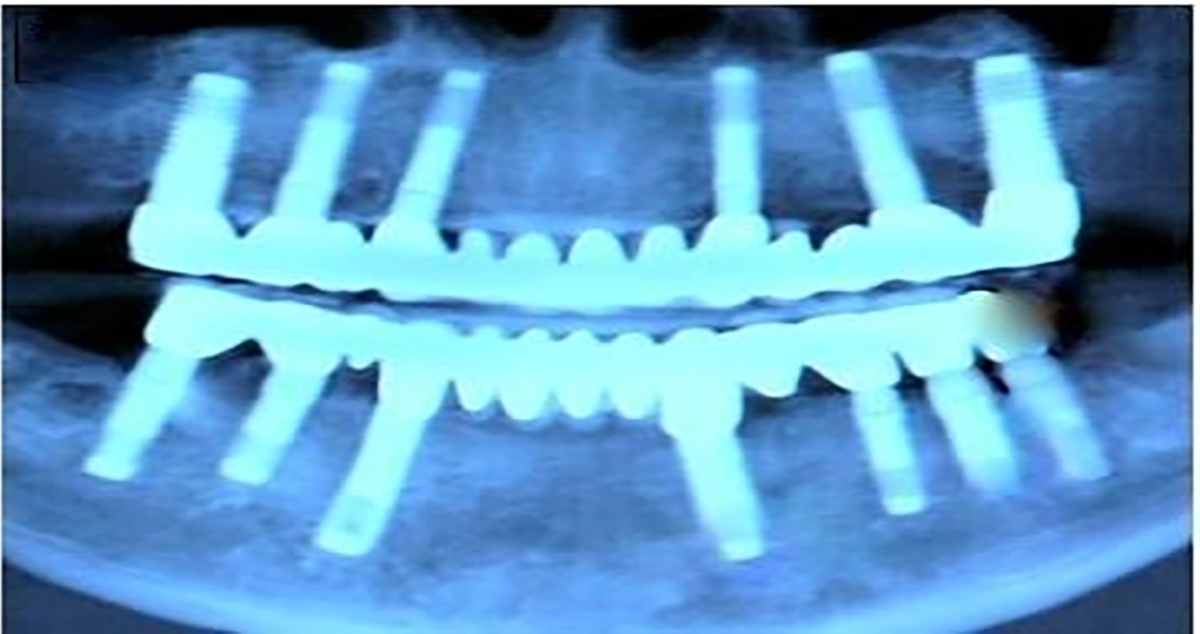

- To obtain full-arch rehabilitation a min. of 6-8-10 implants are adequate, to achieve a predictable outcome.

- Computer-guided surgery minimizes errors in implant positioning.

- Implant position should be uniformly distributed along the alveolar arch and avoid distal cantilevers Implant Design

- The splitting of implants reduces the stresses on the interfaces & enhances the stability, retention, and predictability of implants. The Splinting is attained by using a titanium bar of Ø1.0-1.5 mm, which is welded [19] labiolingually to all the placed implants, close to the gingiva utilizing the intraoral titanium welder [20], and is left in place for 3-4 months’ time. This splinting technique drastically reduces the risk of implant failure during chewing and helps in eliminating or minimizing the damage done by translation or lateral forces thereby evenly distributing the load and lessening the stress over immediately placed fixtures.